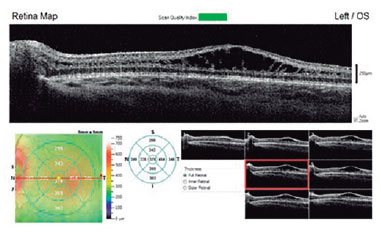

Under general anesthesia, fluorescein angiography (FA) and optical coherence tomography (OCT) were performed. FA and OCT could not be performed in OD due to intense media opacity. FA was inconclusive in OS, revealing no dye leakage in the foveal area with window defects in the mid-periphery. However, OS OCT identified macular schisis with intraretinal separation between inner plexiform and inner nuclear retinal layers, extending beyond the foveal area (Figure 2).

The OS exam was normal, but OS OCT allowed diagnosing XLRS. Hence, the diagnosis was made based on OS assessment, although OD signs were the initial concern.